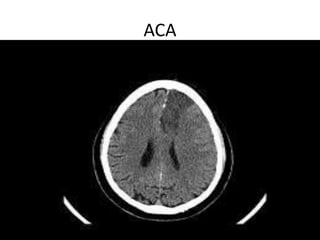

ACA